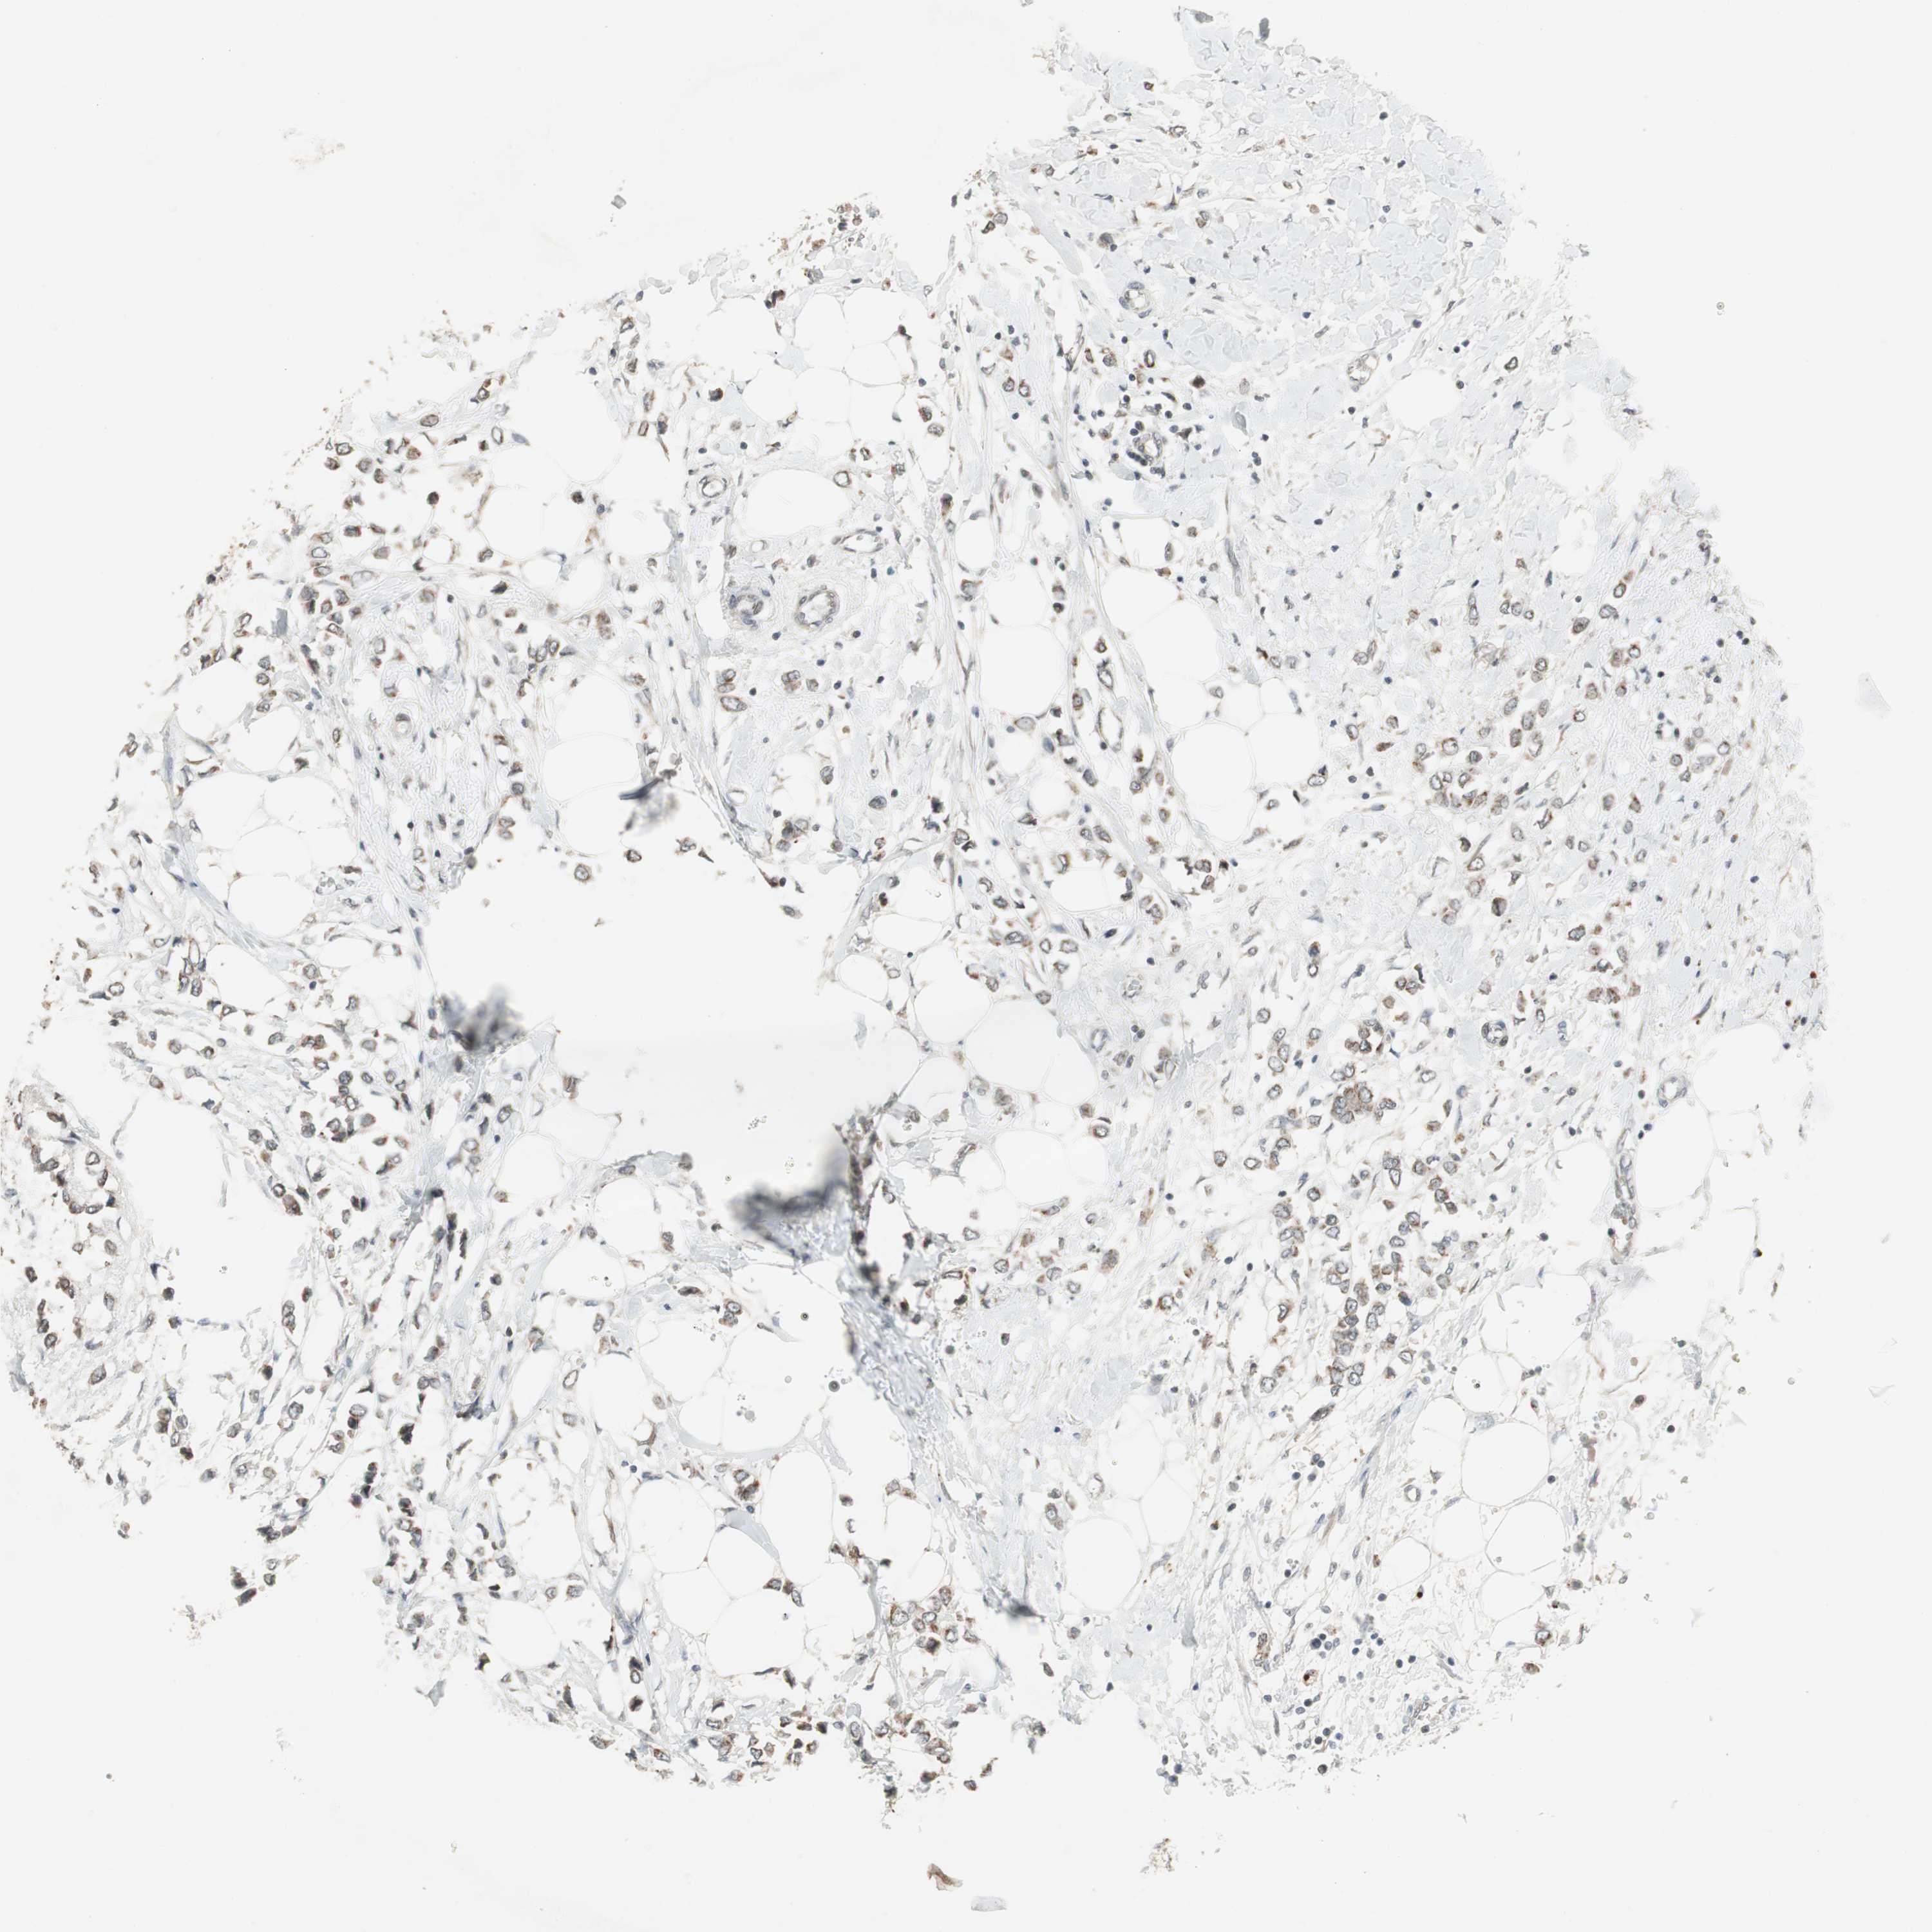

CANCER BREAST CANCER Show tissue menu

BRCA TCGA BRCA VALIDATION PROTEIN EXPRESSION